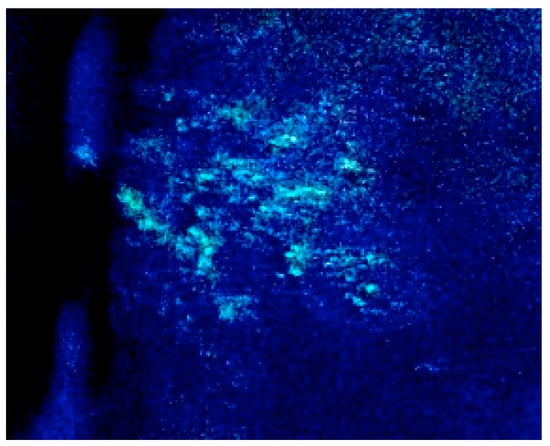

- Selariu, A.; Cheng, T.; Tang, Q.; Silver, B.; Yang, L.; Liu, C.; Ye, X.; Markus, A.; Goldstein, R.; Cruz-Cosme, R.; et al. ORF7 of varicella-zoster virus Is a neurotropic factor. J. Virol. 2012, 86, 8614–8624. [Google Scholar] [CrossRef] [PubMed]